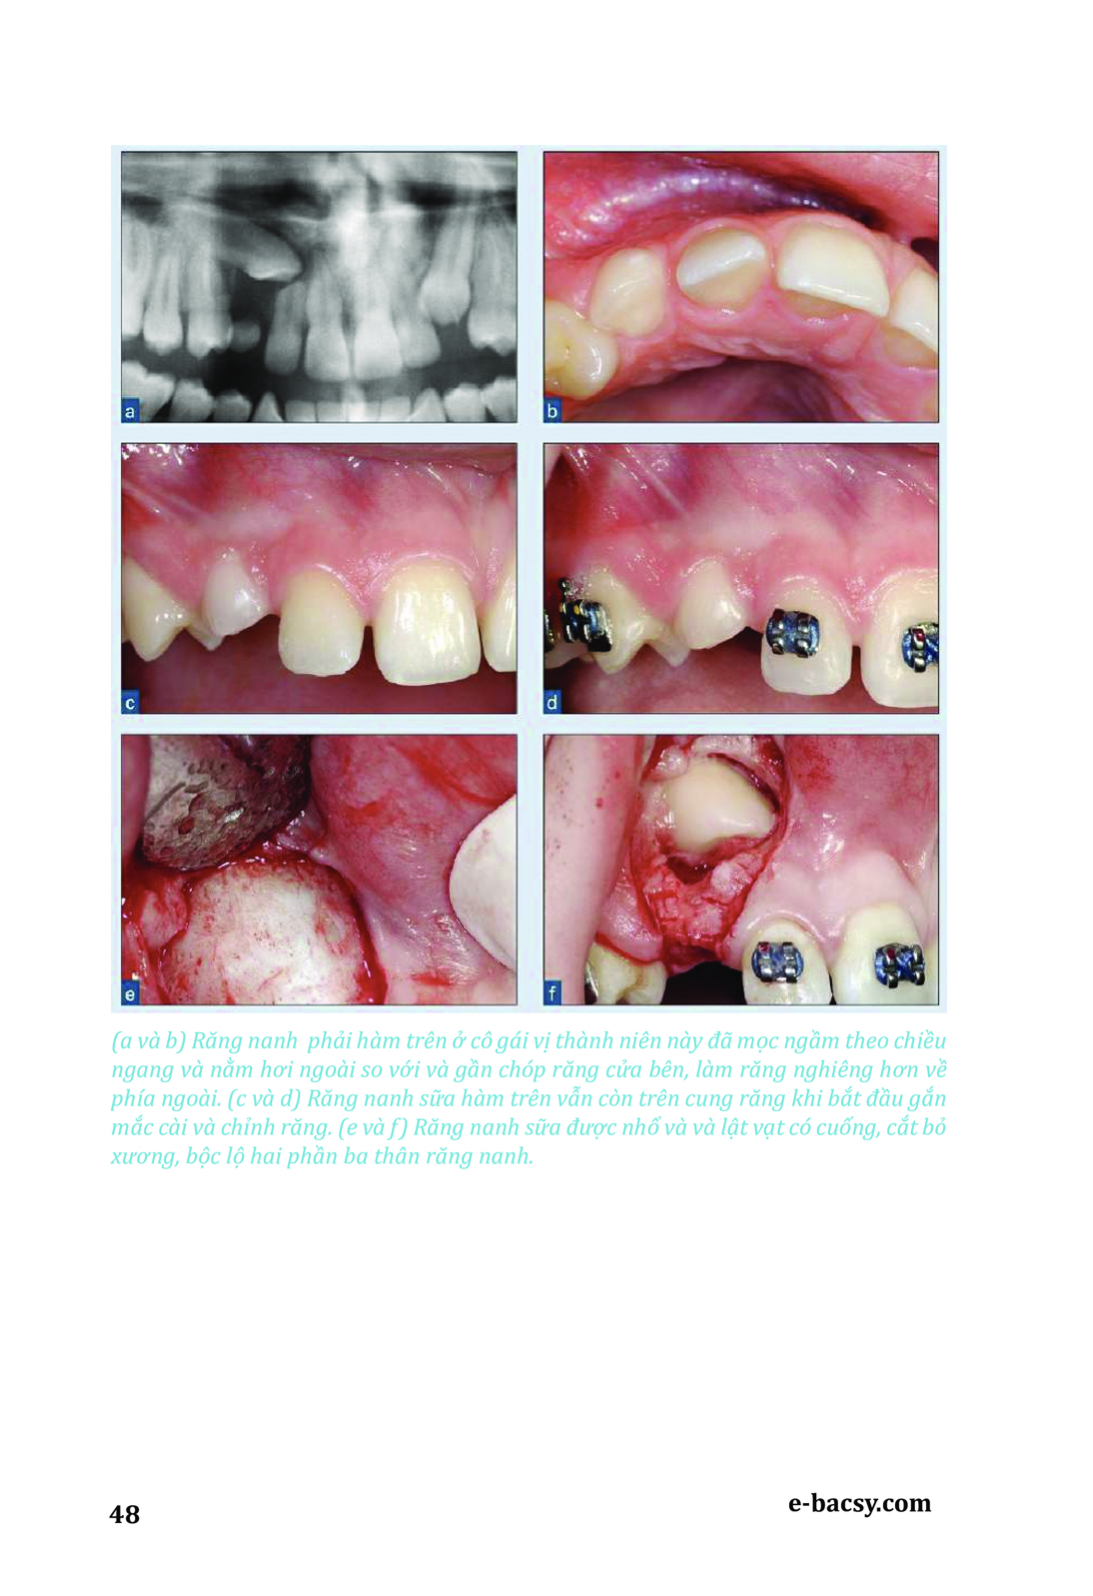

Răng mọc ngầm - Phẫu thuật cùng chỉnh nha